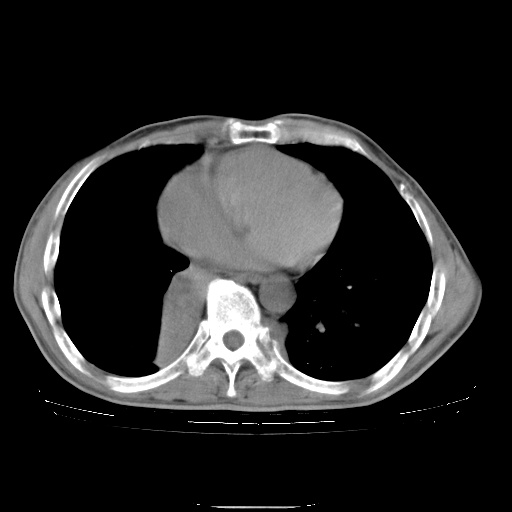

男性患者,63岁。右侧胸背部疼痛2月,加重一周。

考虑:右肺中央型肺癌并右肺下叶不张;两肺尖继发性肺结核。

右下中央型肺癌伴肺内纵膈转移。

右下肺中心型肺癌并肺不张

纵隔淋巴结转移

考虑右中心型肺癌并右下肺不张,肺及纵隔,左肋骨转移。

右肺下叶支气管狭窄闭塞,右下肺不张,气管前间隙淋巴结肿大,两上肺散在分部粟粒灶,沿肺血管支气管束分部,血管支气管束走形较为光滑。考虑右肺中心型肺癌合并肺不张,纵隔淋巴结转移,两上肺癌性淋巴管炎